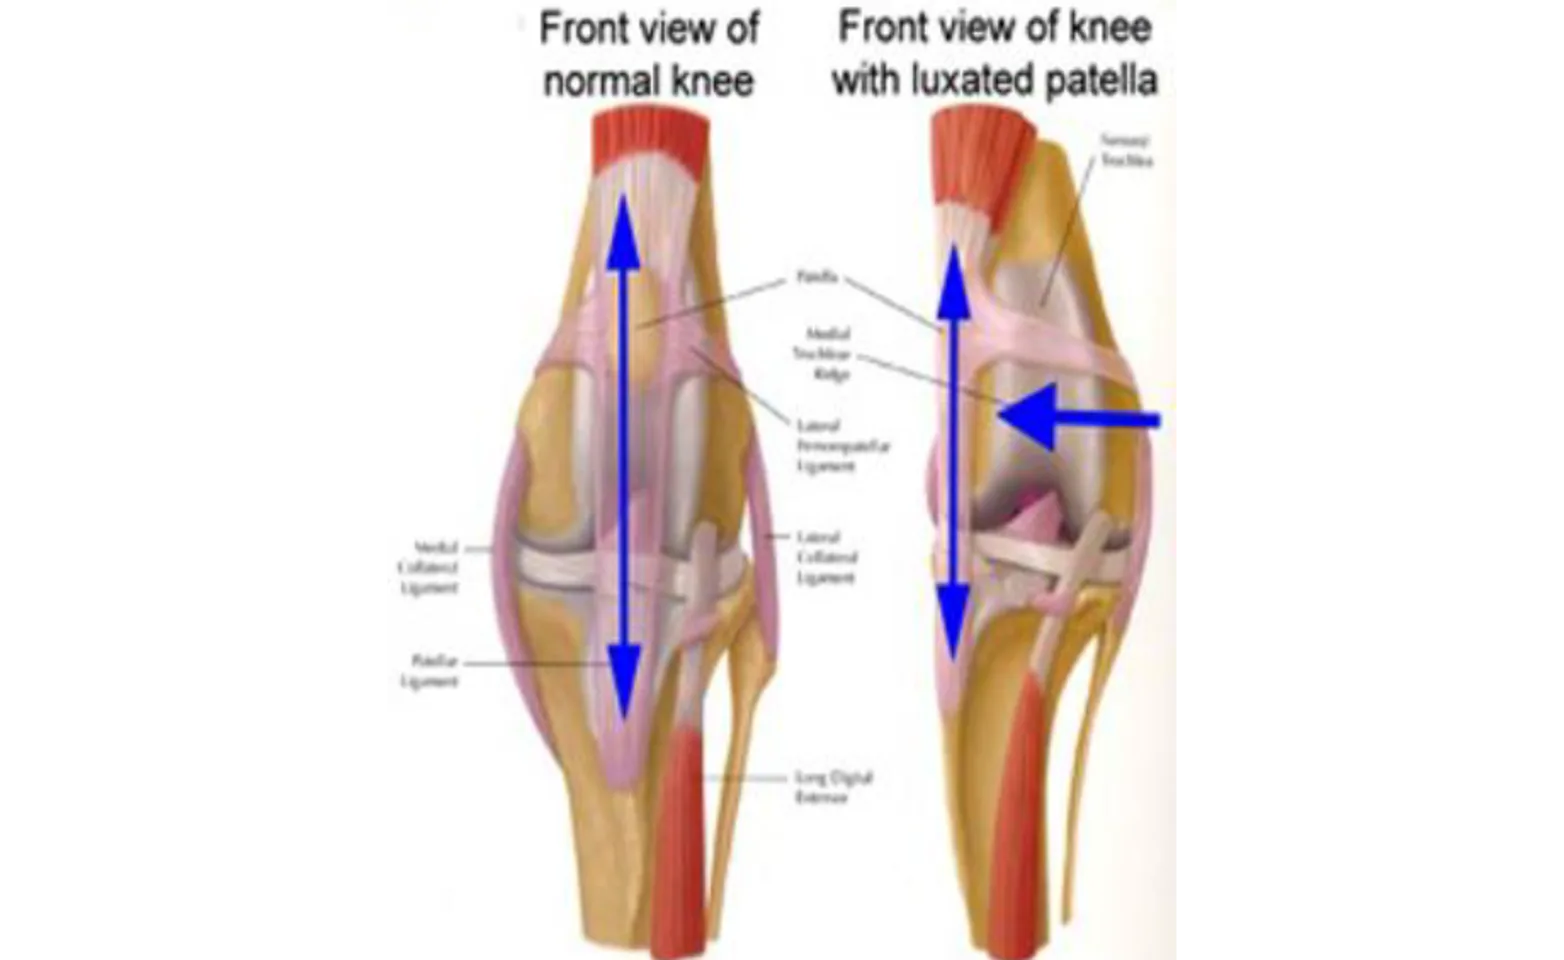

Medial patella luxation (MPL) is a common cause of orthopedic lameness in both small and large breed dogs. In the simplest terms this condition is when the patella, or “knee cap”, slips in and out of its natural position. Normally the patella sits in a groove in the femur and does not move side to side. However, sometimes the patella will be pulled out of this groove, or luxate. The image below illustrates the comparison between the normal canine stifle (knee) and one with a patella luxation.

The radiographs above show a normal canine stifle and a stifle with a Grade IV patella luxation. On the normal radiographs the patella, indicated by the blue arrow, is difficult to see as it lies on top of the femur. In the Grade IV MPL the patella, pointed out by the red arrow, is “floating” in space instead of being properly positioned over the femur. In addition, the femur and tibia are abnormally curved. All of this results in hind limb deformity and persistent lameness or an abnormal gait. (Courtesy Dr. Sharon Kerwin of Texas A&M University)